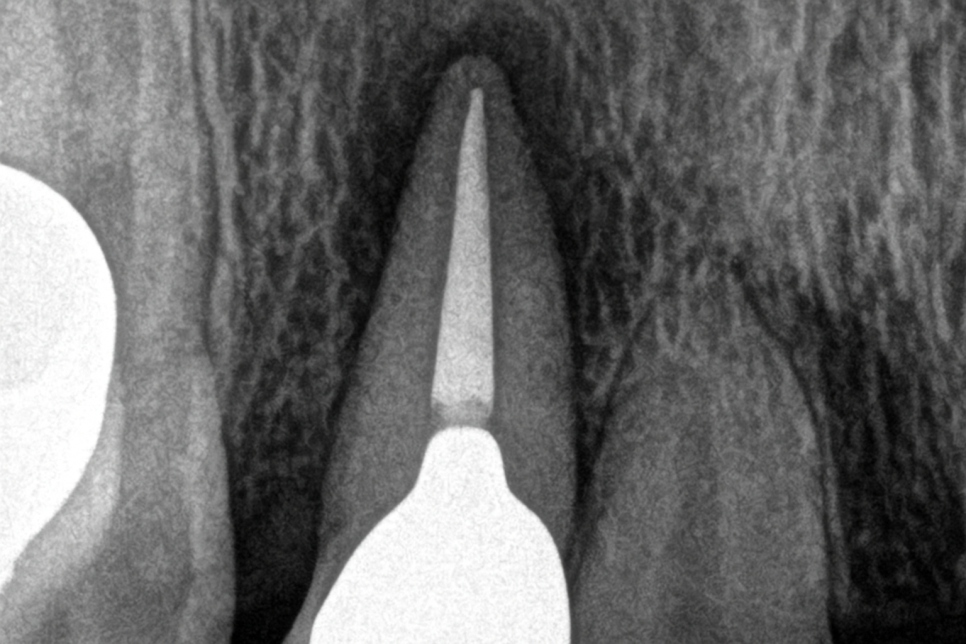

당산동 치과 사진을 보시면 내부 조직이 온전히 제거되어

재료가 채워져 있는 모습이 확인되고 있습니다.

이로써 일전에 신경치료를 받았음을

알 수 있는데 그 후 예후가 불량합니다.

뿌리 끝을 자세히 보시면 치아 주변으로

검게 투과 양상이 뚜렷하게 증가하고 있습니다.

염증이 생겨났기 때문에 검게 보이는 것인데

꽤 넓은 영역에 농덩어리가 생겨나

단순히 재신경치료에 들어간다 해서

긍정적인 차도를 이끌어내긴 어렵다 생각됩니다.

이런 케이스에 적용해 볼 수 있는 게

치근단절제술이랍니다.